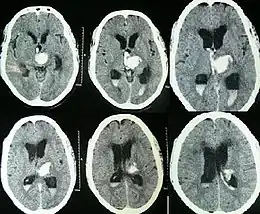

Intraparenchymal hemorrhage can be recognized on CT scans because blood appears brighter than other tissue and is separated from the inner table of the skull by brain tissue. The tissue surrounding a bleed is often less dense than the rest of the brain because of edema, and therefore shows up darker on the CT scan.[30] The oedema surrounding the haemorrhage would rapidly increase in size in the first 48 hours, and reached its maximum extent at day 14. The bigger the size of the haematoma, the larger its surrounding oedema.[31] Brain oedema formation is due to the breakdown of red blood cells, where haemoglobin and other contents of red blood cells are released. The release of these red blood cells contents causes toxic effect on the brain and causes brain oedema. Besides, the breaking down of blood-brain barrier also contributes to the odema formation.[13]

For spontaneous intracerebral hemorrhage seen on CT scan, the death rate (mortality) is 34–50% by 30 days after the injury,[22] and half of the deaths occur in the first 2 days.[51] Even though the majority of deaths occur in the first few days after ICH, survivors have a long-term excess mortality rate of 27% compared to the general population.[52] Of those who survive an intracerebral hemorrhage, 12–39% are independent with regard to self-care; others are disabled to varying degrees and require supportive care.[8]